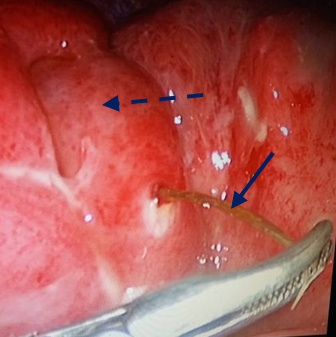

Viêm phúc mạc do tăm tre chọc thủng túi thừa Meckel

Bệnh viện Trường Đại học Y dược Huế vừa phẫu thuật thành công cho một bệnh nhân viêm phúc mạc do tăm tre chọc thủng túi thừa Meckel. Đây là bệnh lý...